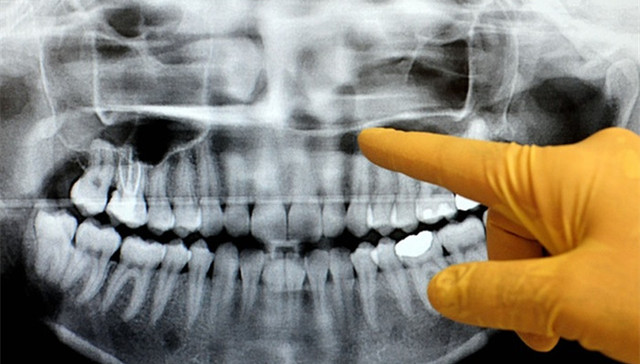

一支由英美两国科学家所组成的团队对比了来自英国成年人口腔卫生调查和美国全国健康营养研究调查中的几千个数据。他们搜集了掉牙齿的样本、成年人对于自己口腔健康的看法,探究了口腔问题对于日常生活(如牙痛、吃东西不方便和不再开口笑等)以及社交生活所造成的影响。此外,他们也调查了患者的受教育程度和家庭收入水平。

研究显示,平均每个美国人的掉牙数量远远高于英国,具体为7.31比6.97,而且美国人更容易因为社会经济因素而导致口腔健康问题的滋生。